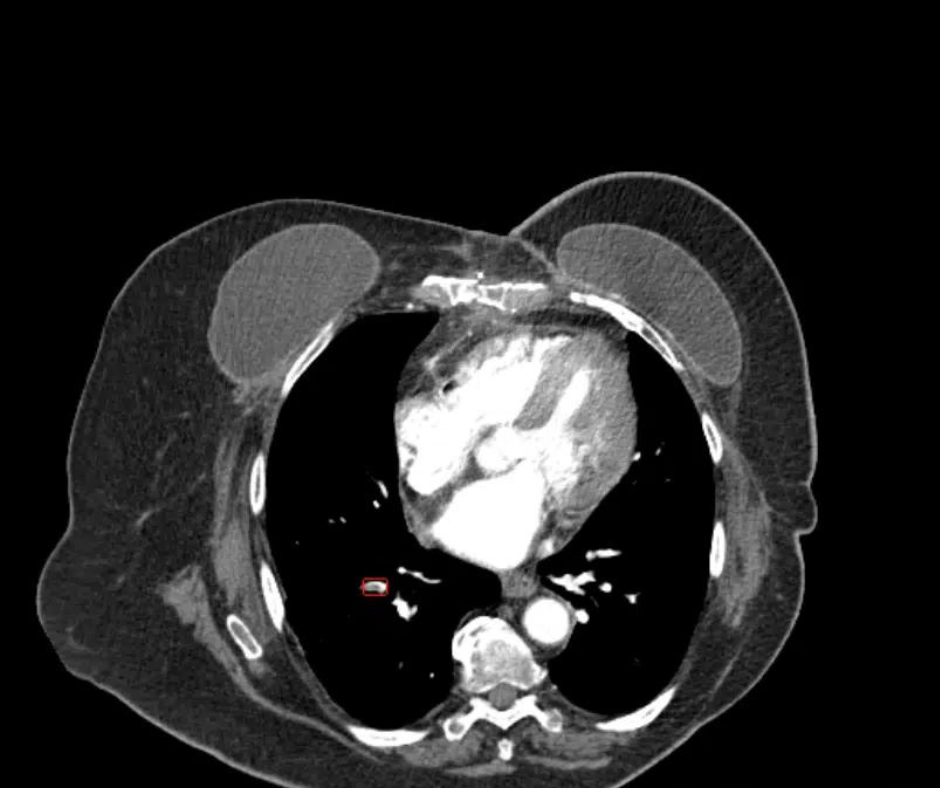

Review the case study and test your knowledge to make the correct diagnosis.